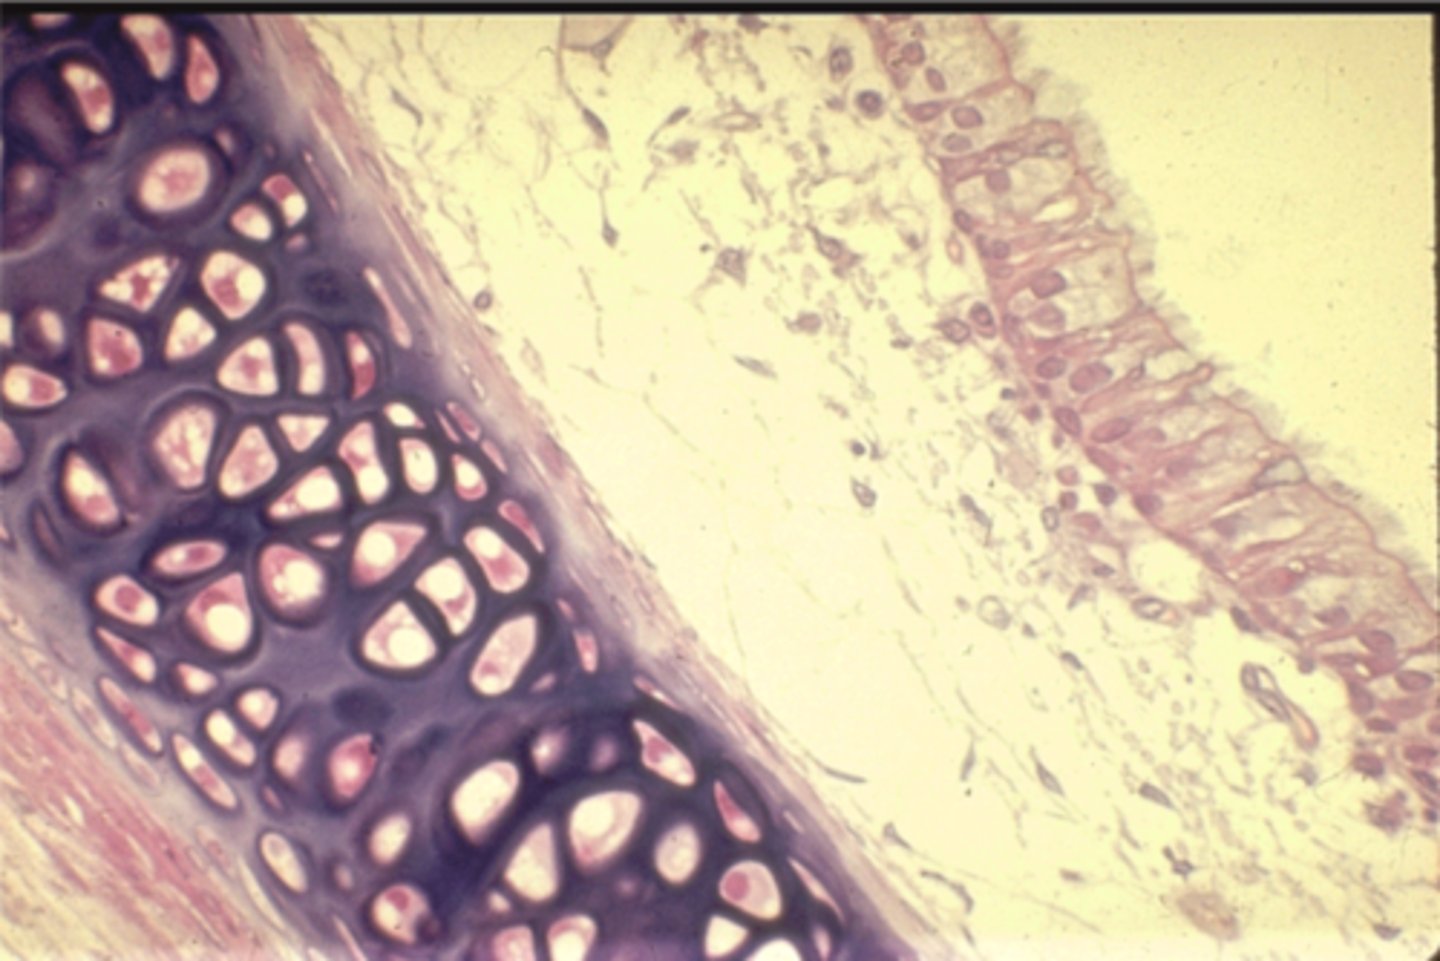

artery

what is this?

vein

what is this?

thicker inner wall

How to identify an artery

thinner inner wall

How to identify a vein